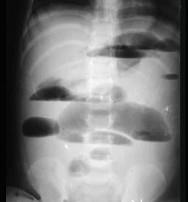

问题 老年人发生机械性低位肠梗阻时,首先应想到 ( )

选项 A、小肠扭转 B、肿瘤所致的肠梗阻 C、粘连所致的肠梗阻 D、蛔虫团所致的肠梗阻 E、嵌顿性腹外疝

答案 B